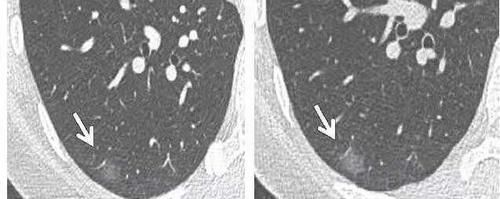

我们先来看第一个病例,如下图:

文章插图

患者第一次体检,查出右肺磨玻璃结节(上图左侧),对于这种结节,我们没有办法确定性质,于是建议随访复查,间隔半年之后,患者复查胸部CT,发现结节有增大(上图右侧),于是立即进行了手术切除,结果术后病理证实为肺腺癌。